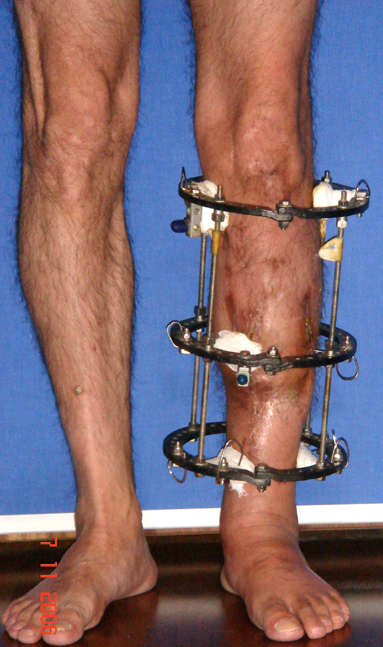

Appropriate radical debridement necessitates excision of all necrotic bone and soft tissues, and frequently causes instability at the involved extremity. The remaining bone and soft tissue defect has to be fixed and reconstructed. The distraction osteogenesis method of Ilizarov is used successfully for achievement of union, correction of the deformity, elimination of limb length inequality and reconstruction of segmental bone defects.

The duration of external fixation (external fixation index) depends on the amount of distraction required, and the extremity is prone to complications during this period. After the distraction phase is completed, the external fixator remains in place during the consolidation phase, which lasts twice as long as the distraction phase; but this period is hardly tolerated. If the external fixator is removed before sufficient consolidation is achieved, fractures, deformity and shortness will be the result. In our department, ‘lenghthening over nail’ method is used in order to decrease the external fixation index and increase patient comfort and activity level. In this method, the intramedullary nail is statically locked after the completion of the distraction phase, and external fixator is removed. The extremity is stabilized by the intramedullary nail during consolidation phase. In this way, complications due to long external fixation index or early removal of the external fixator are avoided.